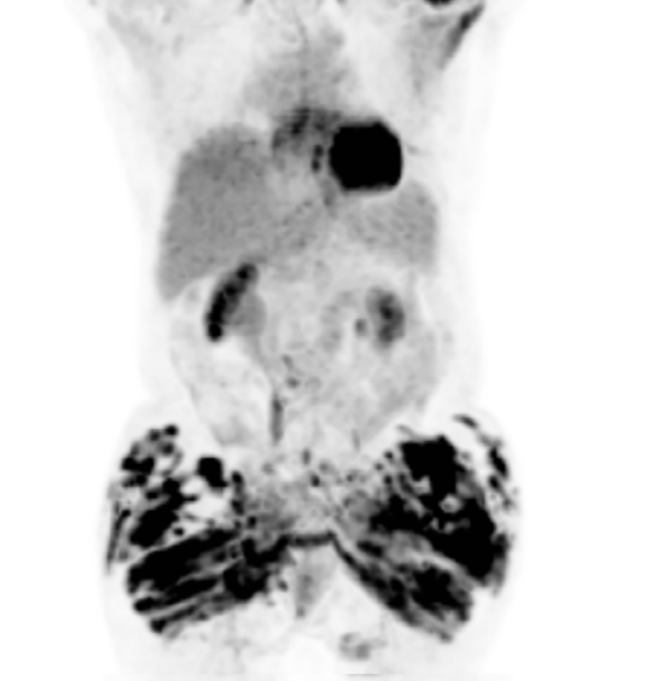

Resumo: Este artigo descreve casos de hipercalcemia grave e lesão renal crônica associadas a injeções de grandes volumes de PMMA para fins estéticos. A hipercalcemia nesses casos se desenvolve devido a uma reação granulomatosa de corpo estranho, secundária à produção extrarrenal de calcitriol.